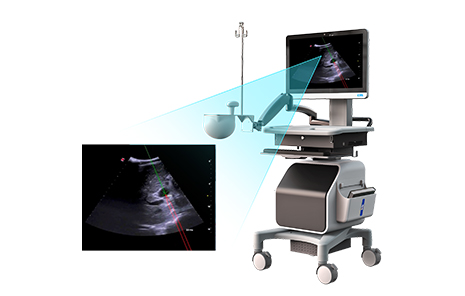

高端医疗器械